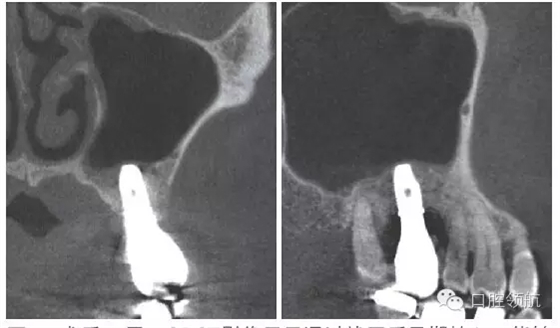

患者,78歲,男性 ,因6 牙齦腫脹來院,檢查見牙根周圍因牙槽骨缺損表現(xiàn)為透過影像(圖1)。在制訂治療計劃時,對于因重度牙周炎、慢性根尖周炎、牙根折斷等原因?qū)е碌难例X缺失需要行上頜竇底提升術(shù)的病例,不能單純考慮缺牙區(qū),要同時考慮鄰牙狀態(tài),并用CBCT確認(rèn)上頜竇底黏膜是否有增厚,這是非常重要的。該病例,根據(jù)CBCT能夠觀察到上頜竇底黏膜增厚,拔牙即刻植入感染幾率較高。計劃拔牙后4~8周,拔牙窩牙齦上皮愈合但拔牙窩未消失時(拔牙后早期植入)植入種植體(圖2)。

圖1 CBCT影像確認(rèn)是由6 引起的上頜竇底黏膜增厚。

術(shù)后12周在獲得骨結(jié)合后,開始制作上部結(jié)構(gòu),術(shù)后16周戴入(圖8)。術(shù)后24周,CBCT影像顯示,種植體周圍有足夠的骨量(圖9)。

圖9 術(shù)后24周,CBCT影像顯示通過拔牙后早期植入,能夠進行安全確實的上頜竇底提升術(shù)。